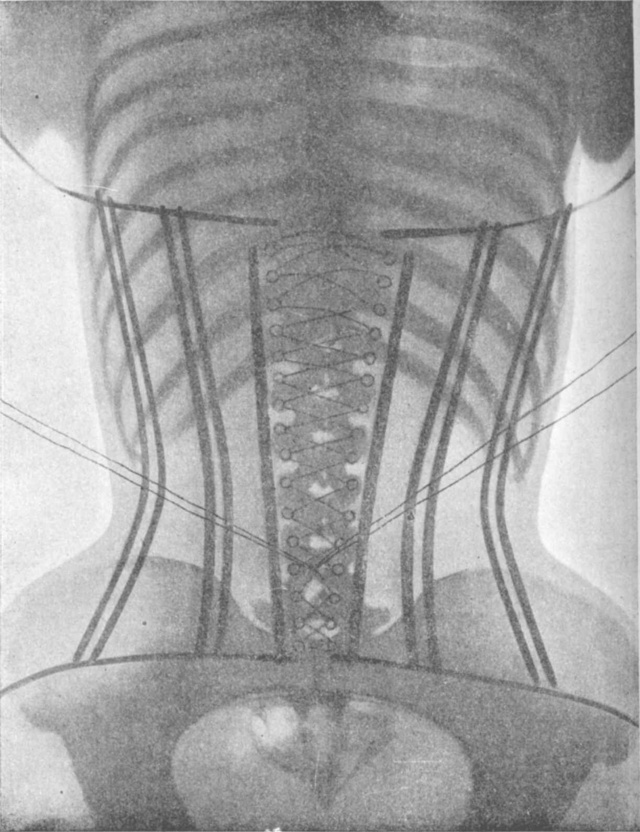

Women’s bodies were never meant to be squeezed into corsets, which is immediately apparent when you check out x-ray images from 1908.

how glad I am that I didn’t live as a fashionably-dresed woman in The GIlded Age,